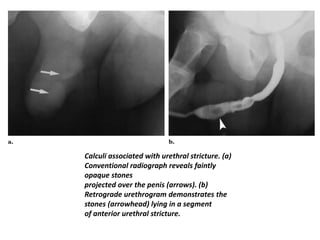

Calculi associated with urethral stricture. (a)

Conventional radiograph reveals faintly

opaque stones

projected over the penis (arrows). (b)

Retrograde urethrogram demonstrates the

stones (arrowhead) lying in a segment

of anterior urethral stricture.